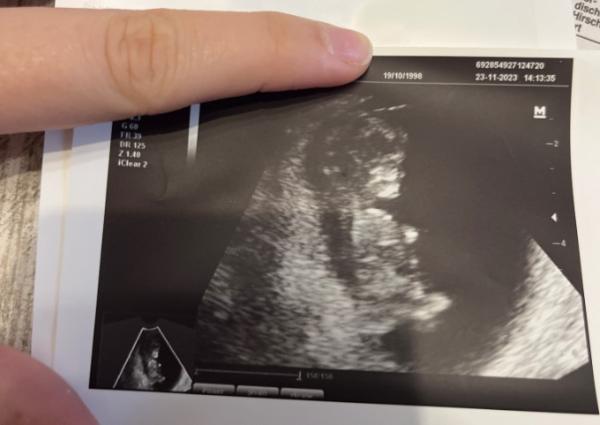

Hallo meine lieben, ich wollte einmal von meiner positiven Gyn Erfahrung berichten. Ich hab schon einige Jahre psychische Schwierigkeiten, die sich aber in den letzten Monaten sehr sehr reduziert haben. Leider hatte ich bis hierhin keine gute Woche. Ich hatte vor 3 Wochen meinen letzten Termin (8+0) und habe meinen nächsten eigentlich erst nächste Woche Donnerstag gehabt. Nun hab ich heute spontan angefragt ob ich vorher noch mal kommen kann, einfach weil ich mich so sorge. Mein Arzt war super offen und hat mir angeboten direkt vorbei zu kommen um mir meine Sorgen zu nehmen. Siehe da, erwartet mich ein kräftiger Herzschlag, strampelnde Arme und Beine und ein quick lebendiges Baby, und mir geht es psychisch so so viel besser. Damit möchte ich euch nur ermutigen, einmal mehr zum Hörer zu greifen, wenn ihr euch danach fühlt und es euch eventuell nicht gut geht. Anbei ein aktuelles Foto von Mucki

Bild zu Sorgen -> Termin - Forum für Juni - Mamis